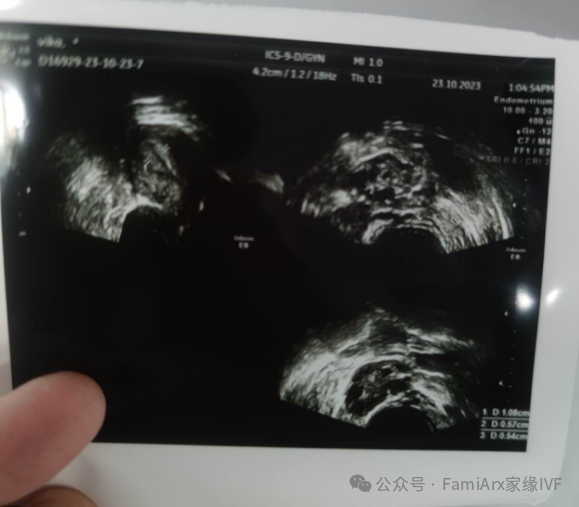

然后我们在10月23号,以10mm的很好的内膜指标进行了移植。

几天后告诉我,她测到了印。然后第十天,就得到了HCG 208.7的好消息。

出胎心的时候,她特别高兴,我们又带她去外面购物和吃饭。